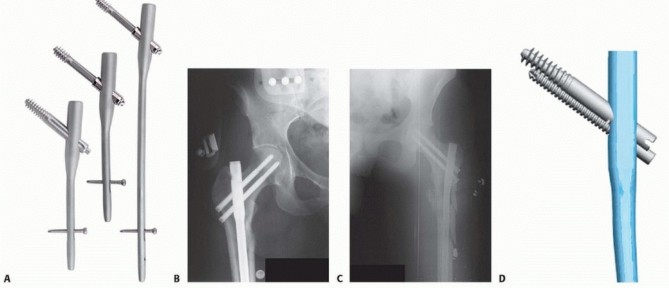

### FIG 3 • Russell-Taylor classification. Type IA fractures are in reality high diaphyseal femoral fractures within 5 cm of the lesser trochanter. Type IB fractures are fractures at the diaphyseal-metaphyseal junction of the proximal femur with medial instability due to fracture comminution in the lesser trochanteric region. Type IIA fractures involve the greater trochanter and lateral wall but have the possibility of restoration of medial cortical stability. Type IIB fractures are the most unstable fractures, with fracture extension into the greater trochanteric region, and have lost medial cortical stability. Russell-Taylor type IIA fractures are fractures involving the greater trochanter and lateral wall but have the possibility of restoration of medial cortical stability. Reverse obliquity patterns fall into this grou If the greater trochanter is displaced, open reduction and stabilization are required. Trochanteric portal cephalomedullary nails are recommended if a nail technique is preferred. Piriformis nails may not obtain sufficient stability of the proximal femur. Open plate and screw reduction with an indirect reduction technique and trochanteric buttress plating may be preferred in this group of patients especially if the greater trochanter is displaced cephalad. 11 Russell-Taylor type IIB fractures are the most unstable fractures, with fracture extension into the greater trochanteric region, and they have lost medial cortical stability by disruption of the lesser trochanteric region. Trochanteric cephalomedullary nails are the preferred nail option for this group if a stable nail construct can be obtained, or alternatively, a proximal femoral locking plate if comminution of the greater trochanter precludes nail stability in the proximal fragment. If the anterior femoral neck is comminuted, accessory fixation and reduction of the anterior wall in conjunction with proximal femoral locked plate fixation is advised. 5 Reverse obliquity patterns and lateral wall fractures occurring in the perioperative period have been identified as high-risk patterns for sliding compression hip screwtype implants. Failure by excessive collapse of femoral neck length and medialization of the shaft is a form of dynamic failure of the implant, and although the implant may survive, the resultant deformity will compromise the patient's functional recovery. Our ability to differentiate stable from unstable pertrochanteric fractures has been shown to be the result of unstable malreductions and unappreciated osteopenia in the shaft and femoral head fixation with implant bone interface failure as the etiology of failure. 7, 16 Determination of the preoperative neck-shaft angle and medullary canal diameter is paramount to selection of the correct nail device, as different manufacturers have different neck-shaft angle and diameter nails. Another important consideration is nail curvature for long nails. Curved nails with a 1.5- to 2-m radius are applicable to most situations, but the surgeon must beware of patients with excessive curvature or tertiary curves in the distal third of the femur, as distal penetration of long nails has been reported. 14 Cephalomedullary nailing involves fixation of the femoral head coupled with an intramedullary shaft implant ( FIG 4). These implants are designed to have a piriformis portal for insertion, usually with the shaft component straight in the AP plane or a trochanteric portal with the shaft component laterally angulated proximally. Modern trochanteric designs have moved to a 4- to 6-degree proximal bend positioned above the lesser trochanteric region, which seems to be most compatible with anatomic restoration of the fracture. 15 Reconstruction design nails (two smaller screws into the head) (Russell-Taylor reconstruction nail and TriGen, Smith & Nephew, Memphis, TN) have the usual advantage of a smaller head diameter (average 13 to 15 mm) and may be of a piriformis or trochanteric portal design, whereas the traditional trochanteric portal (Gamma, Stryker-Howmedica, Mahwah, NJ), intramedullary hip screw (IMHS; Smith & Nephew), and trochanteric fixation nail (TFN; DePuy Synthes, Warsaw, IN) have a single large-diameter femoral head fixation screw or blade and have proximal shaft diameters around 16 to 18 mm. New-generation cephalomedullary nails are moving to smaller geometries of 12 to 15.5 of the head to maximize bone conservation in the proximal femur and avoid excessive bone removal from the lateral wall. New designs in femoral head fixation are also in use with constraint in the reconstruction-type two-screw design to minimize Z-effect (Targon PFN, Braun, Bethlehem, PA) and integrated interlocking two-screw fixation (InterTAN, Smith & Nephew) with the design goal of improving fracture construct rotational and translational stability. 391

- FIG 4 • Cephalomedullary nail types from Smith & Nephew, Inc. A. Gamma class IMHS. B. Piriformis TriGen reconstruction nail. C. Trochanteric TriGen reconstruction nail. D. Integrated interlocking InterTAN nail. (A,D: Courtesy of Smith & Nephew, Inc., Memphis, TN.)